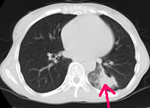

胸部CT

陰になっている部分や小さい病変もよくわかります。

| 胸部CT | 12,100円 | 咳・痰・胸痛など | 肺癌・肺炎・肺気腫など |